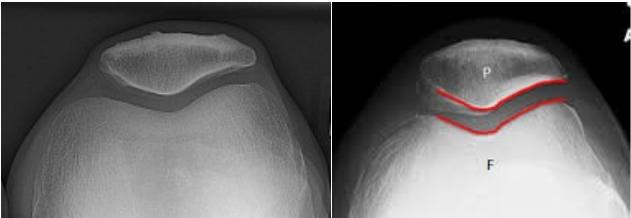

- Skyline (patellar view)